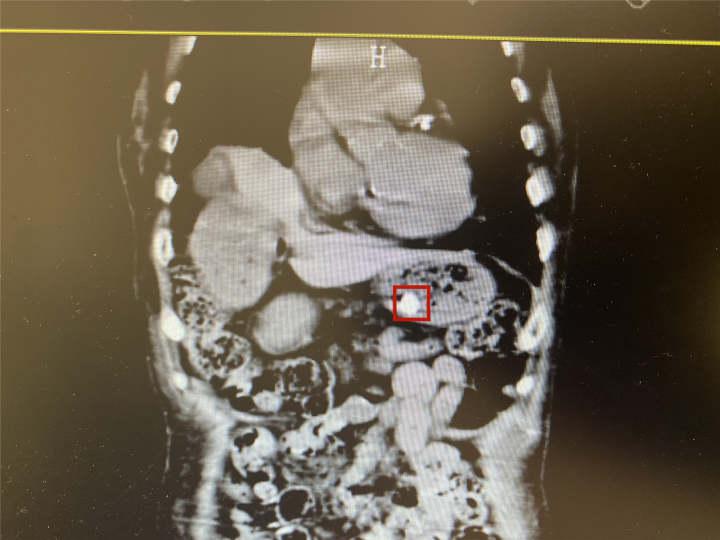

之后,王雷对沙奶奶进行相关影像学检查后,确认假牙在胃里,但考虑到假牙附带金属支架,金属支架上的钢爪随时都有可能划破沙奶奶的胃壁。

情况危急,王雷立马联系集团总院消化内科主任医生陆静静远程会诊,考虑各方因素,最终决定由陆静静主任在宗瑞院区内镜中心行胃镜下异物取出术。

由于老人刚进食没多久,食物还未被消化,一堆食物残渣成了胃镜寻找假牙的拦路虎,护士长提议用网篮翻找,但因食物残渣实在过多,影响镜下观察视野。

此时,陆静静灵机一动,采取边胃镜下冲洗边由胃管吸引胃内容物的方式。经反复冲洗及抽吸,视野渐渐清晰,看见一颗牙齿,但假牙金属边框迟迟未见,决定再次网篮翻找。

最终,在双重寻找下,沙奶奶假牙的金属支架终于在她私人抽屉中被寻到,陆静静则再次确认情况,确保不存在危险后,将老人转回颐养中心休养。